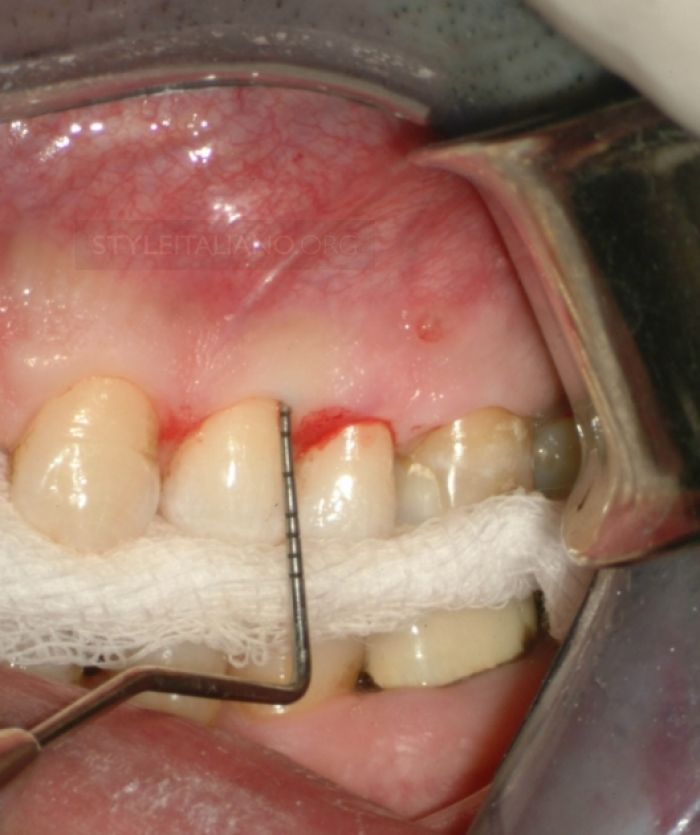

During the procedure, a small flap is created in the gum to access the root tip, the infection is cleaned thoroughly, and the root end is sealed with biocompatible material. Periapical surgery helps eliminate chronic infection, alleviates pain, and restores the tooth’s long-term stability.

Periapical Surgery Procedure

At EndoElite, Periapical Surgeries are performed using advanced magnification systems, microsurgical instruments, and high-quality sealing materials. Our goal is to eliminate infection completely, promote natural bone healing, and preserve your tooth with the highest success rate.